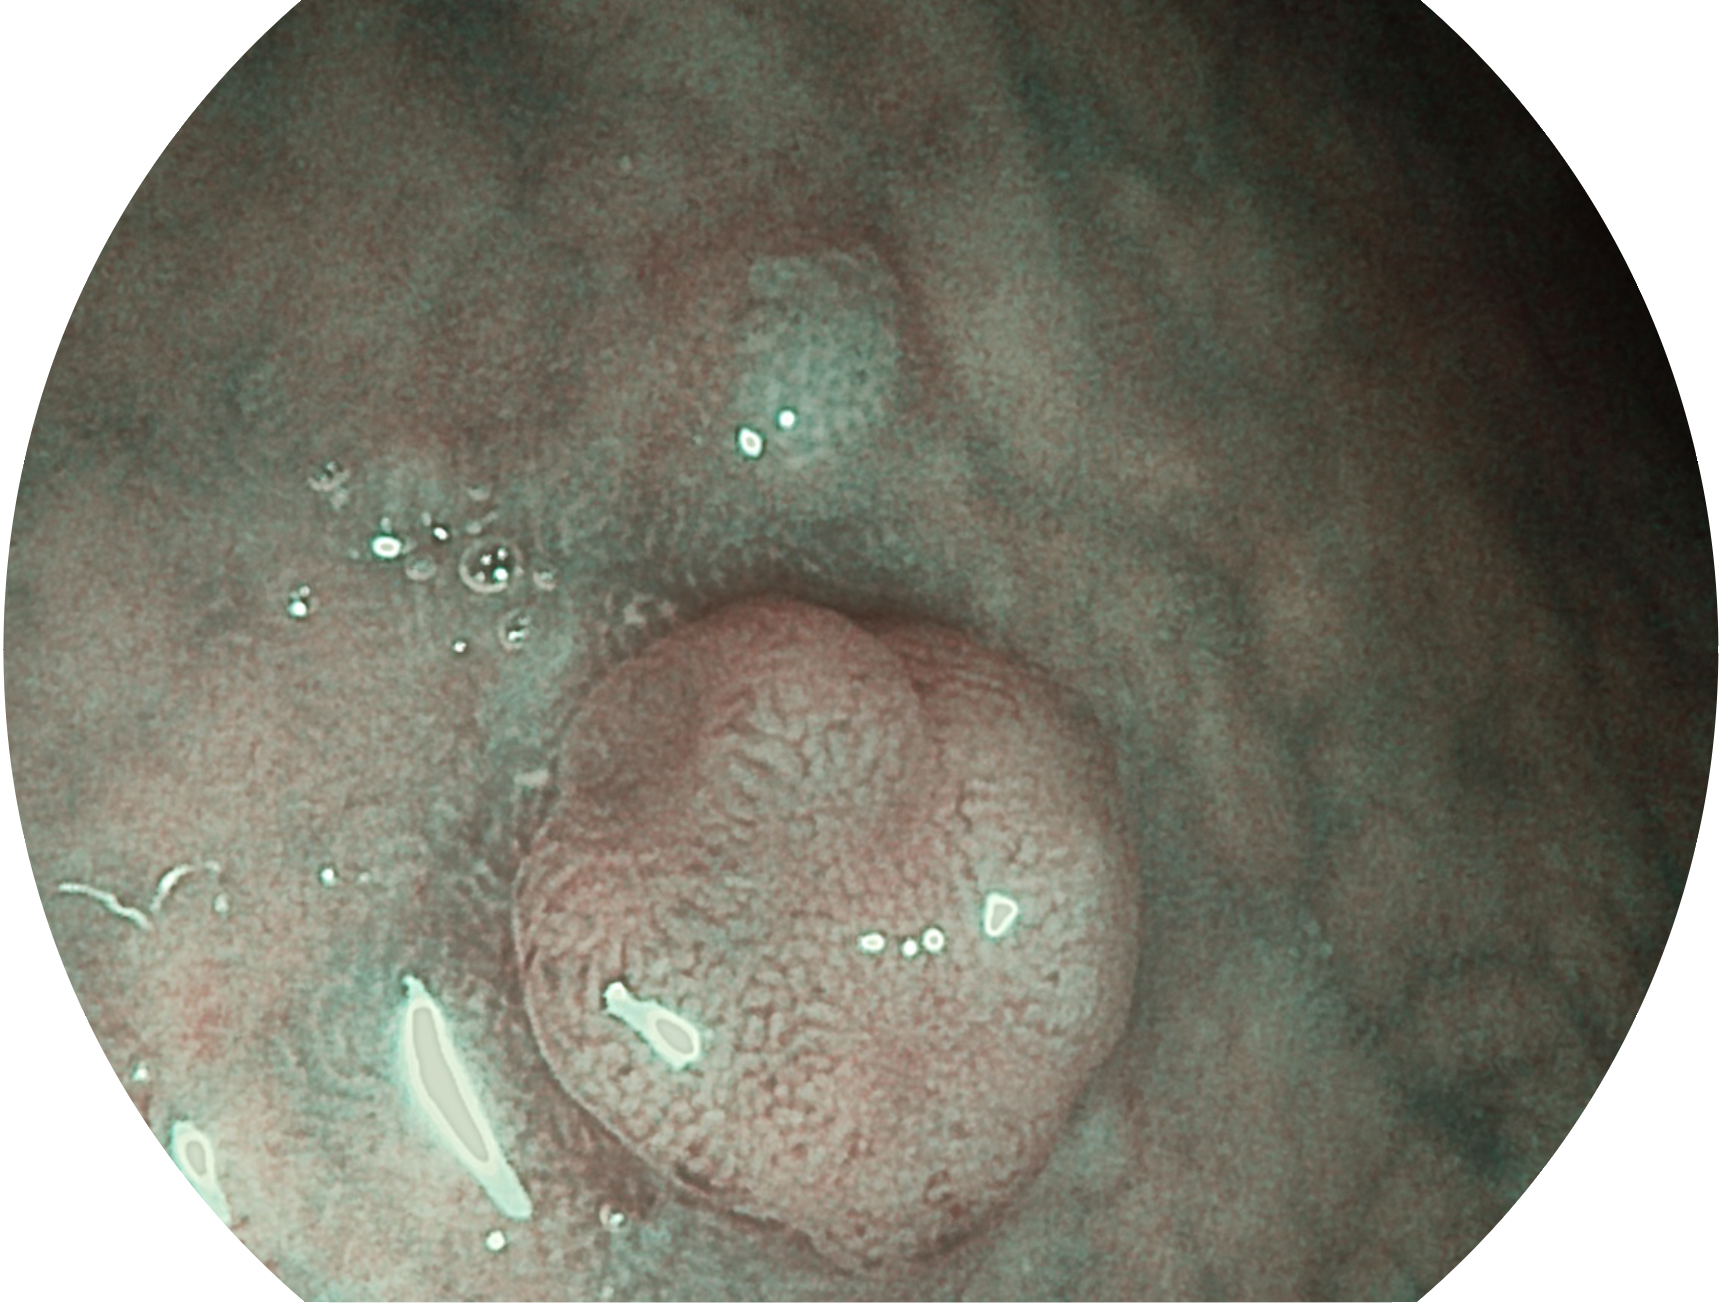

竞技宝(JJB)官方网站新开发的内镜染色技术,主要是基于多波长LED 光源的开发,VLS-55Q 四波长LED 光源是由四个不同颜色的LED光按照相应照明模式所规定的特定发光比例进行合束后形成,合束后形成的照明光的光谱由红光、绿光、蓝光及蓝紫光这四个不同的波段范围构成。具有更高光谱自由度,通过光谱比例的控制,实现了聚谱成像技术,英文全称为“Spectral Focused Imaging, SFI”,缩写为“SFI”和光电复合染色成像技术,英文全称为“Versatile Intelligent Staining Technology, VIST”,缩写为“VIST”。